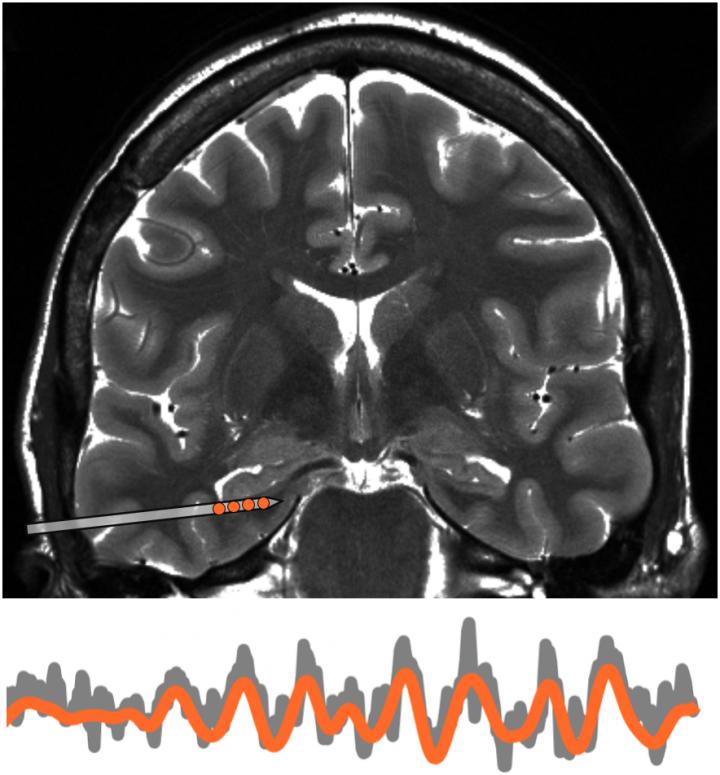

Suthana and her colleagues observed epilepsy patients whose brains had been surgically implanted earlier with electrodes to control their seizures. The electrodes resided in the medial temporal lobe, the brain center linked to memory and suspected to regulate navigation, much like a GPS device.

"Earlier studies have shown that low-frequency brain waves by neurons in the medial temporal lobe help rodents keep track of where they are as they navigate a new place," said first author Matthias Stangl, a postdoctoral scholar in Suthana's lab. "We wanted to investigate this idea in people--and test whether they could also monitor others near them--but were hampered by existing technology."

As the participants searched the room, their brain waves flowed in a distinctive pattern, suggesting that each person's brain had mapped out the walls and other boundaries. Interestingly, the patients' brain waves also flowed in a similar manner when they sat in a corner of the room and watched someone else approach the location of the hidden spot.

The finding implies that our brains produce the same pattern to track where we and other people are in a shared environment.